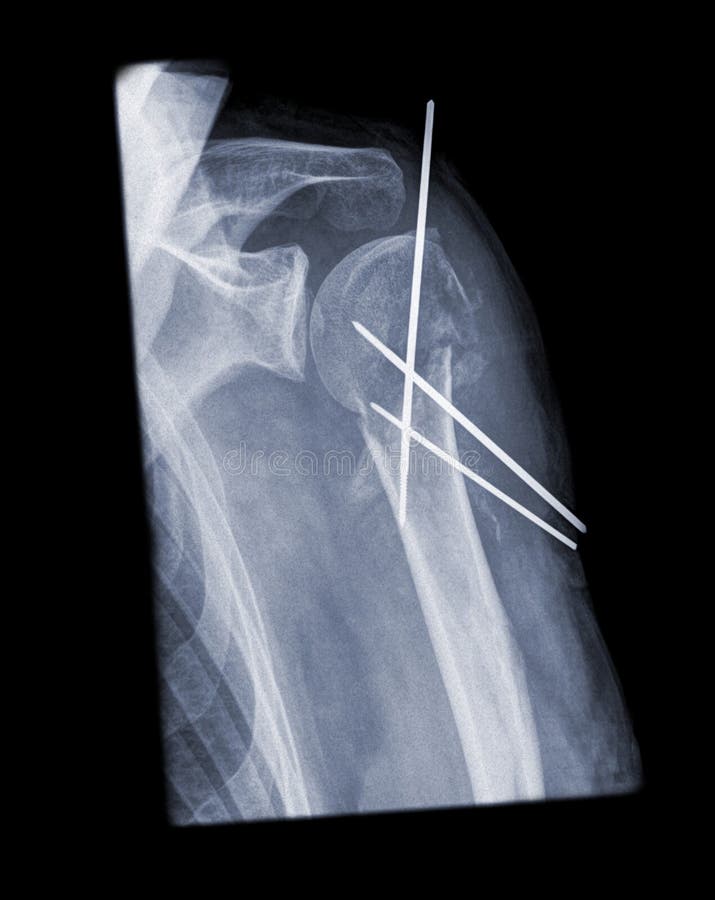

Выделенное коленчатое соединение. 3d представило иллюстрацию боли в локте